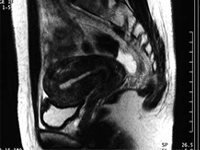

塞栓術前

塞栓術治療3日後

塞栓術治療1年後

黒く抜けているのは全て壊死におちいった筋腫

1年後枯れた筋腫は排出され消失している